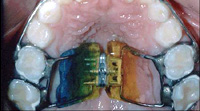

Teeth respond to the gentle forces that are applied to them. “Braces” are a combination of “brackets” and “wires”. Brackets are the part of the braces that attach to the teeth. Brackets are the “handles” that help control movement of the teeth. Braces require a wire called an “archwire” that connects the brackets and provides the forces to steer the teeth in the proper direction. It’s actually the wires that move teeth. The interaction of brackets and archwires enables the orthodontist to have three-dimensional control over the movement of the teeth. In many cases, additional forces are needed to help balance the underlying jaw structure and to help the upper and lower teeth fit properly together to make the bite right. Examples of these extra forces include: elastics (rubber bands) hooked to teeth (see photo below); functional appliances; and palatal expanders (see photo below).![]() |

| Rubber bands provide additional forces to move teeth | A palatal expander |